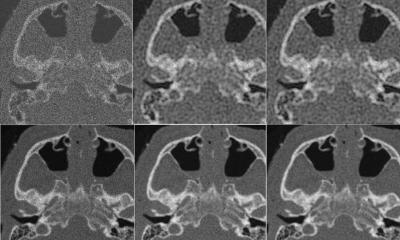

Ultrasound based platforms in this class include the Fibroscan from Echosens, the Siemens S2000, S3000, Philips iU22, and the Aixplorer from SuperSonic Imagine. All systems are capable of quantifying tissue stiffness, but only two produce an ultrasound image.

‘Siemens’ Acuson S3000 produces a still image on which you can take measurements, whereas SuperSonic’s Imagine’s shear wave elastography technology produces a real-time, moving image, which is a significant improvement and is probably the pre-eminent of the technologies,’ the professor pointed out. The first results of the global QIBA initiative, presented at the RSNA congress in December 2013, showed very low inter-observer variation on phantoms, ‘a reassuring result,’ according to Prof. Cosgrove. Currently a study of so-called confounders, like inflammation and liver congestion, is underway with the Harvard Medical School at the Massachusetts General Hospital. A second generation of phantoms featuring a viscous component that simulates fat content, or steatosis, will now make the rounds of QIBA participating centres worldwide.